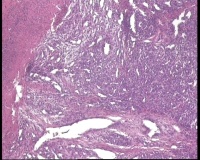

镜下见皮肤鳞状上皮破溃,见多个血管腔,内皮细胞增生,核大,是肉芽肿性毛细血管瘤吗

化脓性肉芽肿

肉芽肿性毛细血管瘤

肉芽肿性/分叶状毛细血管瘤